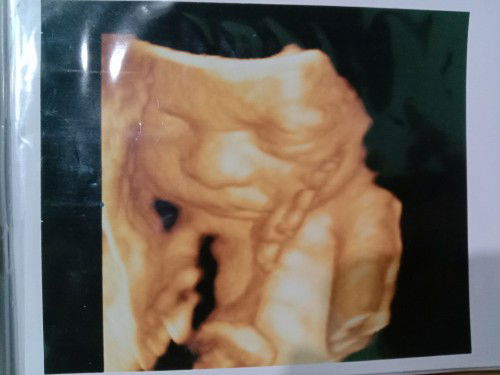

Hai bun, saya sudah lewat HPL 3 hari. HPL 26 Agustus dan sampai sekarang perut cuma kenceng aja. Tadi USG ke dokter kandungan dan hasilnya semua normal dan bagus. Ketuban cukup, plasenta juga masih bagus, kepala sudah di panggul. Hanya saja belum merasakan kontraksi yg rutin. Lalu saya diresepkan obat Misoprostol, diminum 2x sehari. Adakah bunda disini yg pernah diresepkan obat ini oleh dokter ?? Efeknya seperti apa ya ?? Dan berapa lama waktu yg dibutuhkan obat ini untuk bereaksi?? #seriusnanya #bantusharing #ingintahu #firstmom #pleasehelp #firstbaby